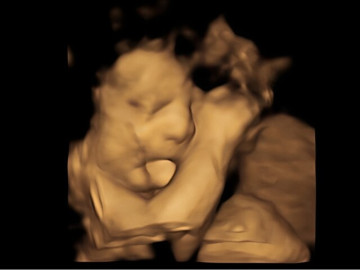

Người cha cho biết: "Khi bác sĩ chỉ tay vào màn hình và nói rằng: 'Đứa trẻ đang giơ hai ngón tay kìa'. Và tất cả chúng tôi đều nhìn thấy khoảnh khắc thú vị ấy và bật cười vui vẻ. Dường như con gái chúng tôi cảm nhận được sự xuất hiện của cha mẹ nên đã giơ hai ngón tay biểu hiện sự chào hỏi, vui mừng".

Em bé giơ hai ngón tay giống như gửi lời chào đến bố mẹ.

Bố mẹ em bé chắc hẳn sẽ cảm thấy hạnh phúc khi bắt gặp hình ảnh con yêu giơ tay chào và há miệng cười to trong bụng mẹ.